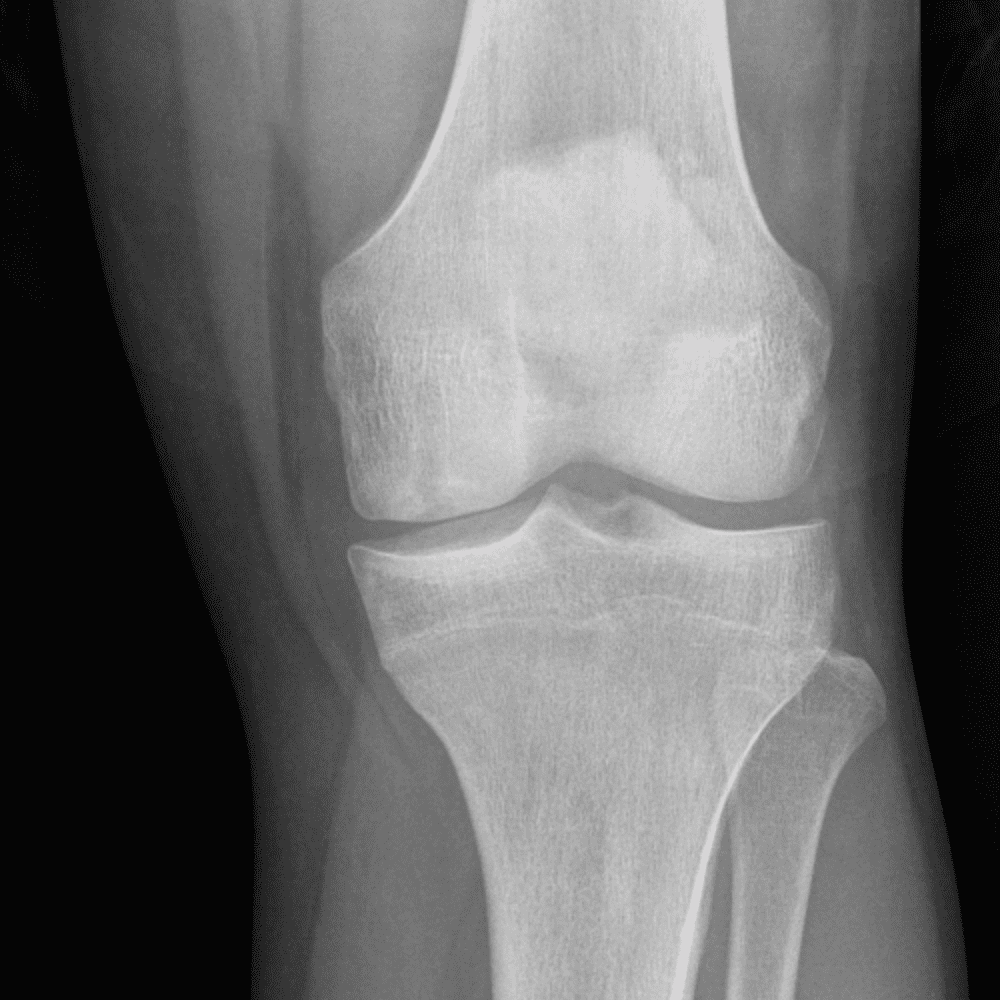

Simula o plantão incluindo casos sutis ou difíceis e alguns normais.